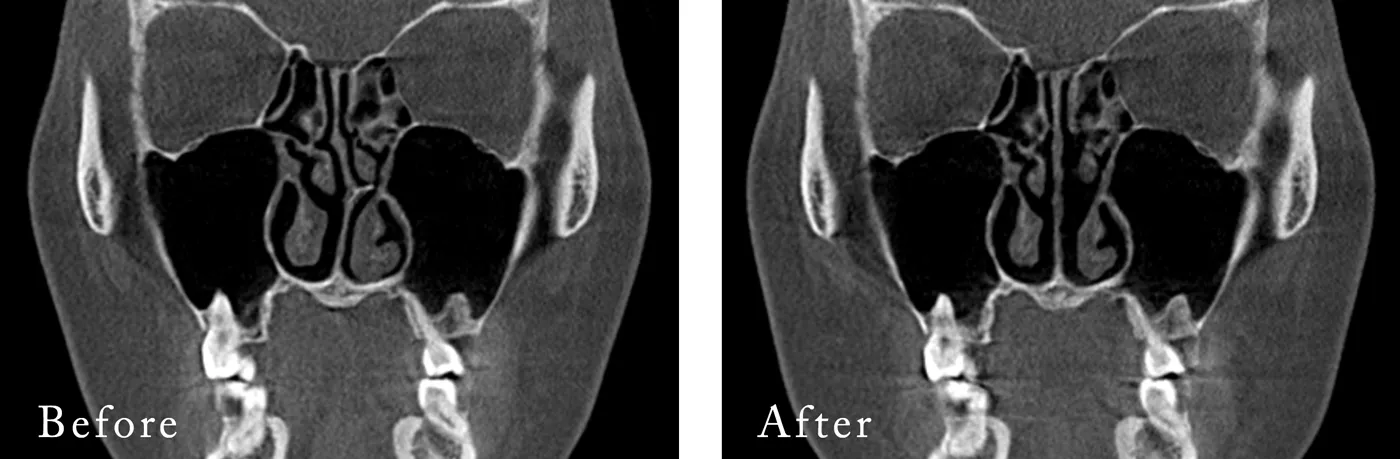

▼鼻中隔湾曲修正を行った方のCT

標準的な費用 鼻中隔湾曲修正

単独¥440,000(税抜¥400,000)

他の手術と併用の場合¥330,000(税抜¥300,000)標準的な施術時間 15分 麻酔 全身麻酔¥220,000(税抜¥200,000)/

静脈麻酔¥110,000(税抜¥100,000)

※ザ・プラス美容外科では、全身麻酔による手術につきまして麻酔科専門医の医師が担当しております。